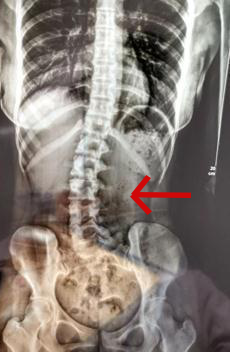

医生检查发现其脊柱严重侧弯,x光检查提示,她的腰椎向右侧弯、旋转,并以腰2椎体为中心向右侧弯,脊柱向右发生明显侧弯。

小邹的脊柱明显侧弯

“患者是因为其睡姿不当,原有正常的脊柱体态在日积月累的错误睡姿中逐渐失衡,骨盆与脊柱位置变化,脊柱就发生了侧弯。”医生介绍。